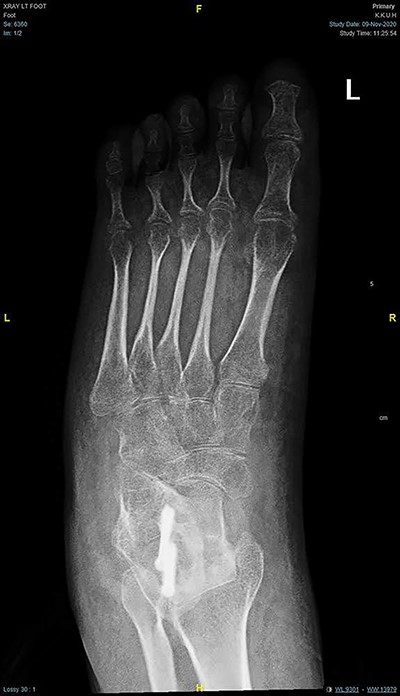

Magnetic resonance imaging (MRI) brain and whole spine were ordered for her due to the neurological pattern of the disease. The MRI showed T4–T5 posterior fusion, there were no other neurological lesions. For evaluation of the varicose veins, vascular consultation was obtained, and Doppler ultrasound was ordered, which showed absent popliteal deep veins. Radiography of the left foot revealed marked cavus as well as hindfoot and forefoot varus. Also, it showed soft tissue swelling, reduction in bone density, and no evidence of fracture or dislocation or tarsal coalition (Fig. 2). The right foot radiograph was unremarkable apart from mild hallux valgus deformity (Fig. 3).

AP radiograph of both feet showing cavovarus deformity of left foot and right hallux valgus.